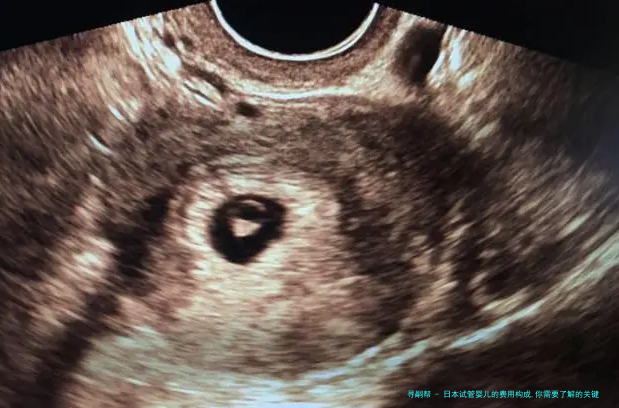

日本试管婴儿技术在全世界声誉卓著,吸引了很多夫妻前往求医。然而,认识日本试管婴儿的费用构成是每位求医生必须留意的关键点。下列是关于日本试管婴儿费用构成的细致说明。

首先,日本试管婴儿的费用主要包括以下若干个部分:

1. 诊断费用:在开始试管婴儿疗程前,医生会对夫妻双方进行全方位的身体检查,以评介生育本事。这单方面费用平常在1万至2万元之间。

2. 药物费用:试管婴儿疗程中,女性需打算使用洪量药物来刺激排卵和预备子宫内膜。药物费用因各别差别而异,平常需花费两万至4万元。

3. 手术费用:试管婴儿手术囊括、胚胎培育和胚胎移植等环节。手术费用约为3万至5万元。

4. 试验室费用:胚胎培养和基因筛查等实践室操作须要高昂的成本。这部分费用一般来说在2万至4万元。